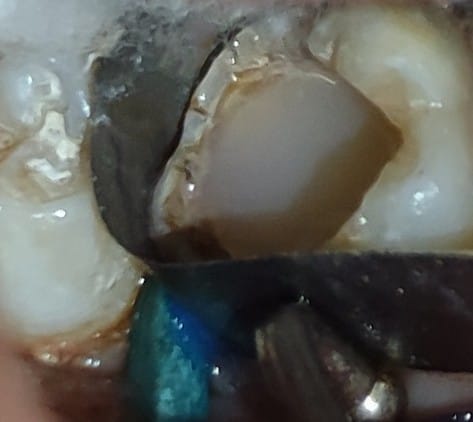

after 6 months, the tooth shows visible apical constrictions and patient had no pain. redone the temporary restoration and again put patient on 6 months follow up for complete apex formation.

after another 6 months the tooth show complete apex formation and patient had no pain, did the root canal treatment, and packed with composite.